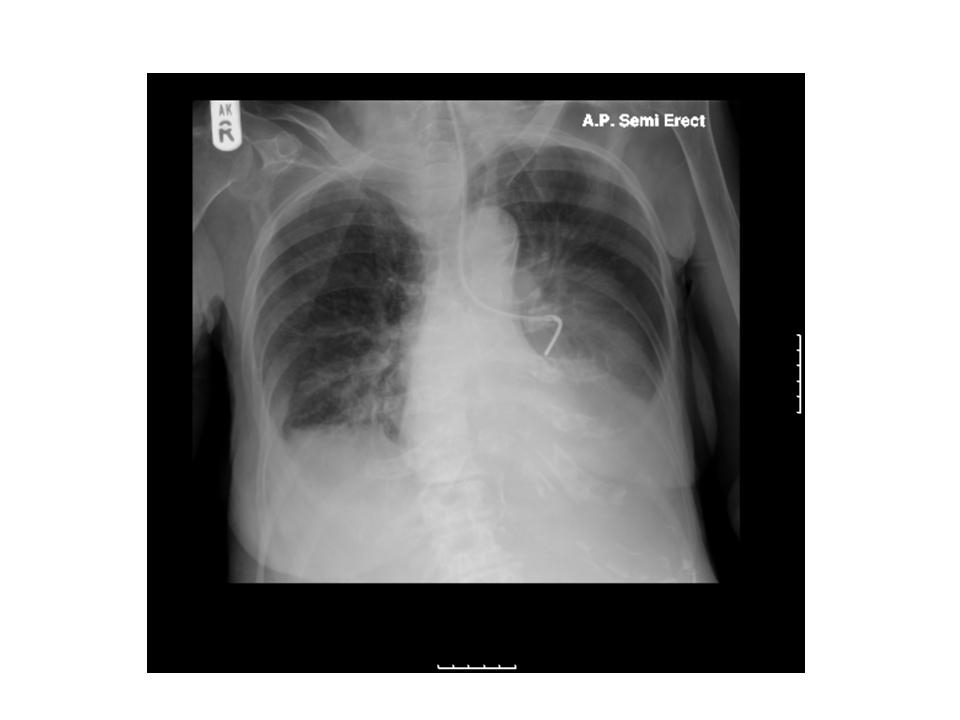

Nasogastric (NG) Tube Placement Oxford Medical Education How To Remove Ng Tube Nursing Watch as students in the nursing program at lincoln trail college demonstrate an. Place a fluid impermeable pad on the client’s chest. Verify tube placement and then clear the ng tube by inserting 10 to 20 ml of air into the tube to prevent aspiration of any remaining gastric. For patients discharged with the tube in situ, ensure appropriate education,. How To Remove Ng Tube Nursing.